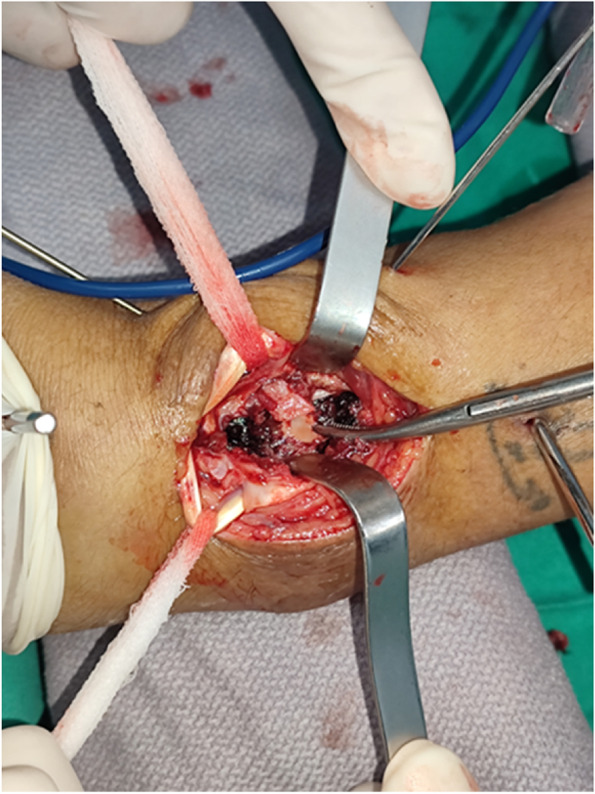

Fig. 1.

Auxiliary dorsal approach for reduction. After incision of the joint capsule, bone fragments were seen directly

If the articular surface was compressed or the intra-articular bone fragment was still displaced, the distal end of the plate screw was temporarily fixed with 1–2 shorter screws to maintain the length of the radius and the position of volar fragments. Then, a dorsal incision was made along the Lister tubercle. The distal end crosses the radiocarpal joint line and ends at the 1 cm proximal end of the base of the second metacarpal carpal joint, and the proximal end extends 3–4 cm along the radial trunk. The intermediate column was exposed through the bottom of the third extensor space. The extensor retinaculum was severed along the extensor longus tendon and then released and protected. The distal end of the extensor retinaculum was cut in a "V" shape so that the distal end of the extensor longus tendon can maintain its original path and later cover the plate as a soft tissue flap. Peeling along the periosteum revealed the intermediate column, and peeling along the second extensor compartment revealed the dorsal side of the distal radius. A limited incision of the joint capsule was made along the dorsal margin of the radius to observe the surface of the joint, and the compressed or collapsed intra-articular fracture fragment was exposed and elevated (Fig. 1). If necessary, bone defects after reduction can be treated with allogeneic bone. After reconstructing the articular surface, the dorsal fragments were fixed with a dorsal plate or Kirschner wires. Then, we went back to the volar incision, and the longer screws of the distal VLP were applied and finished the final fixation. The surgical incisions were closed layer by layer by suturing. Finally, we used a short-arm plaster splint for immobilization in the first week and then let patients begin gentle active exercises.